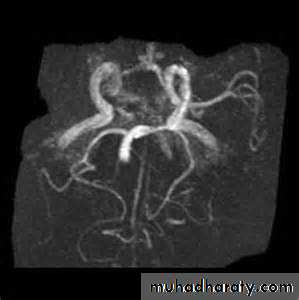

• CT angiography permits screening of large and medium-sized vessels for AVMs, vasculitis, and other arteriopathies.• MR angiography permits screening of large and medium-sized vessels for AVMs, vasculitis, and other arteriopathies.

• Conventional catheter angiography definitively assesses large, medium-sized, and sizable small vessels for AVMs, vasculitis, and other arteriopathies

Consider catheter angiography for

• young patients

• patients with lobar hemorrhage

• patients without a history of hypertension

• patients without a clear cause of hemorrhage who are surgical candidates.

CT angiography

MRI angiographyCatheter MRI angiography